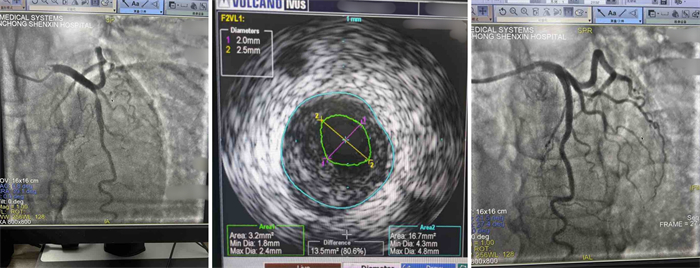

结合患者冠脉造影结果及患者年龄相对年轻,黄洪团队决定在IVUS(血管内超声)指导下精确植入支架1枚。手术顺利完成后,该名患者胸痛、胸廓压榨不适感、颈部梗阻感等症状完全消失。为了表达对医生的感谢之情,他特意送来锦旗,感谢医务人员这段时间的精心照料。